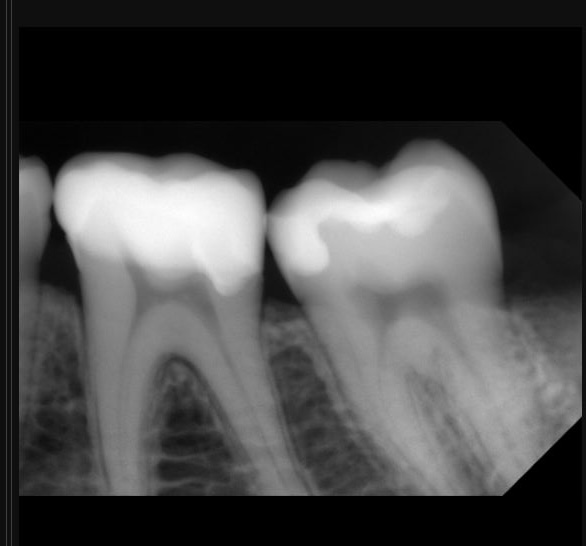

3.6 in-direct resin ceramic

3.6 is not recommended for direct restoration due to the thickness of the cusps.

The patient did not experience any spontaneous pain in the mandibular first molar cavity